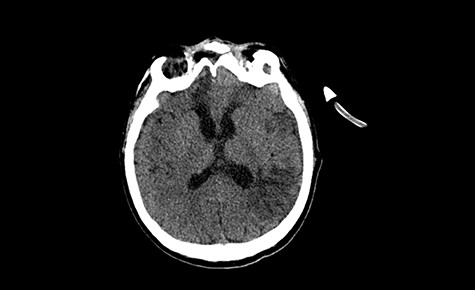

A 49-year-old patient presented after surgical treatment of nasal polyps, with headache and consciousness disorders (behavioral changes, drowsiness and allophenic orientation disorders). Computed tomography (CT) scan showed (Fig. 1) a presence of blood in fluid spaces, widening of the ventricular system (without active hydrocephalus features) and presence of air in the frontal horns of the lateral ventricles and features of cerebral edema. Due to the subarachnoid hemorrhage, an angio-CT and CT scan was performed, showing no vascular malformation. The patient's condition deteriorated with a drop in Glasgow Coma Scale (GCS) to 9, strongly expressed meningeal syndrome and a fever of > 38°C. In the performed cerebrospinal fluid examination a typical picture for bacterial infection, cultures negative. Treatment was implemented in accordance with the neuro-infections algorithm. Clinical and laboratory features of neuroinfections have withdrawn. The neurological condition of the patient improved to GCS 11. Control head CT (Fig. 2) showed enlargement of the ventricular system with cerebrospinal fluid transudation.

Head CT—state before VP shunt implantation. (Department of Neurosurgery own material).

After improvement of patient’s neurological status, a CT scan of the head revealed enlargement of the ventricular system with the features of cerebrospinal fluid transudation (Fig. 2), thus the patient has been qualified for a VP shunt implantation (Fig. 6).